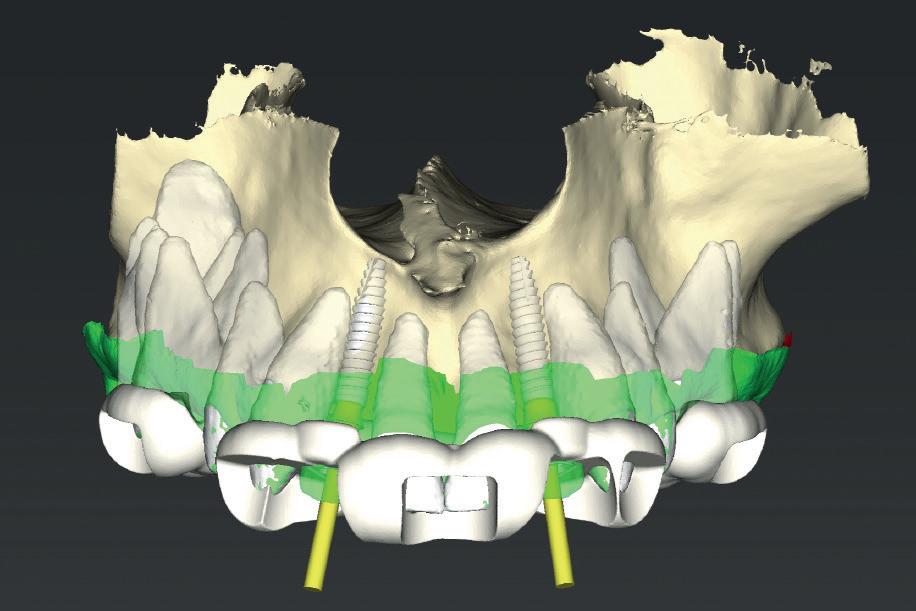

CASE STUDY

Guided implant approach for reproducible results, page 28

1. Adaptable to different guided surgery protocols: piloted, semi-guided or fully guided.

2. No friction between drills and guide sleeve, no overheating and no release of particles.

3. No specific drills and a very small surgical box.

4. Full control of drilling depth.

5. Your conventional driver-guided drilling sequence.